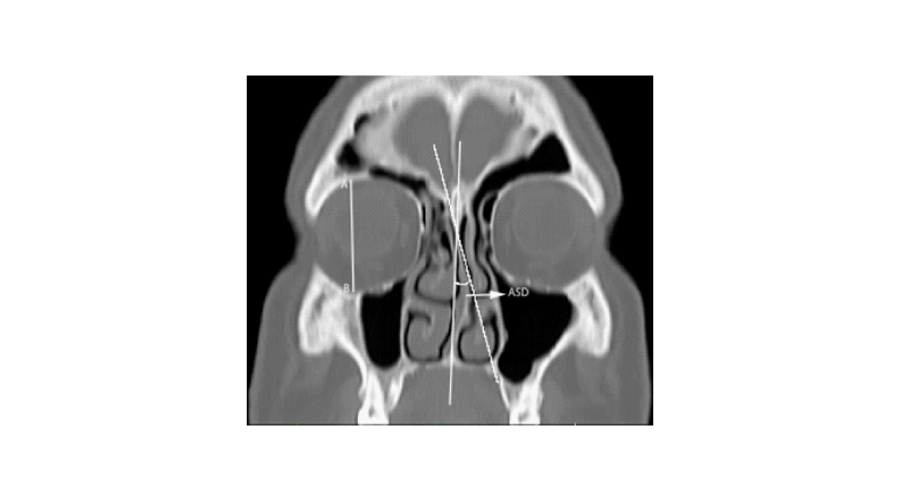

The angle of the septal deviation (ASD): the angle between a line drawn from the maxillary spine to the crista galli and another line from the crista galli to the most deviated point of the nasal septum was accepted as the deviation angle on the coronal plane (Figure 3).

Figure 3:

The maximal height of the orbit in the vertical plane was measured in each patient on the coronal plane (Figure 3). In order to eliminate the influence of individual variation, the ratio of maximal orbital height to the measured parameters were used for analysis. The calculated ratio values compared among the groups. Each measurement was performed two times by the first author, at different times. Because the measurement points were clearly described, measurements were consistent.